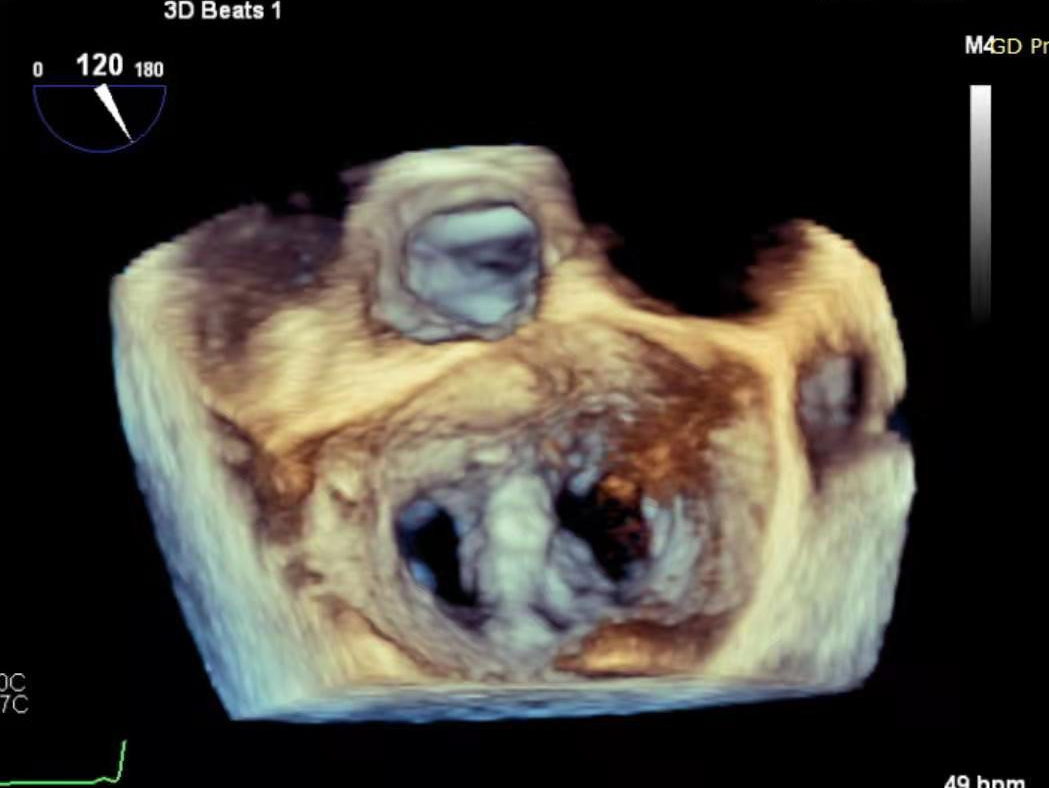

术前,罗建方、范瑞新教授团队进行了多次缜密术前讨论,最后决定为患者采用DragonFly™二尖瓣瓣膜夹。经充分的术前讨论后,心内科罗建方、范瑞新教授团队,在超声指导下,麻醉和体外循环团队保驾护航,瓣膜夹平稳释放,成功植入一枚DragonFly™瓣膜夹,随即进行DSA及心脏超声复查,观察到植入的瓣膜夹位置精确,患者二尖瓣反流从4+减少到1+以下,手术取得了圆满成功。